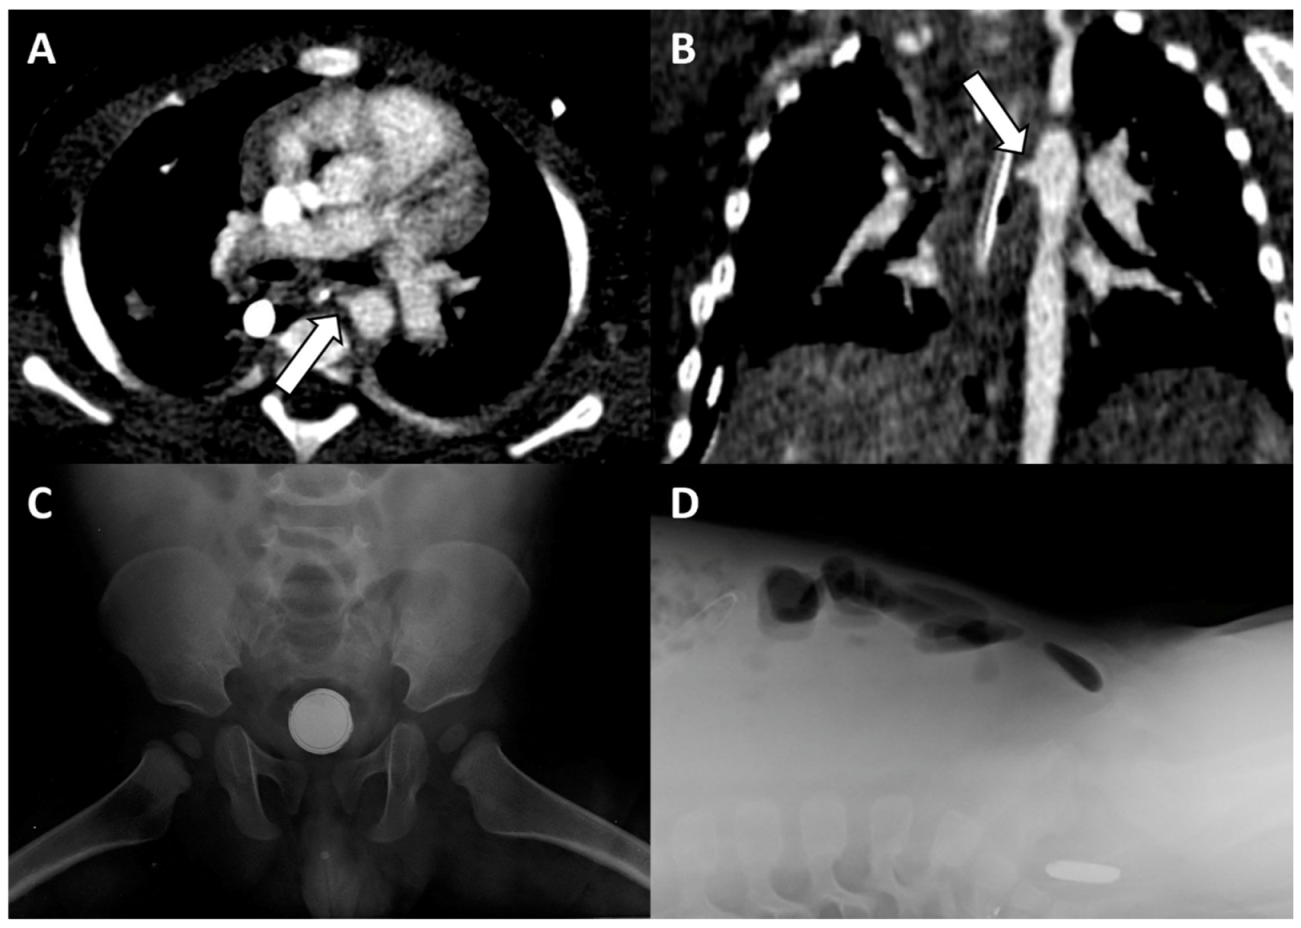

2. Case 1

3. Case 2

4. Discussion